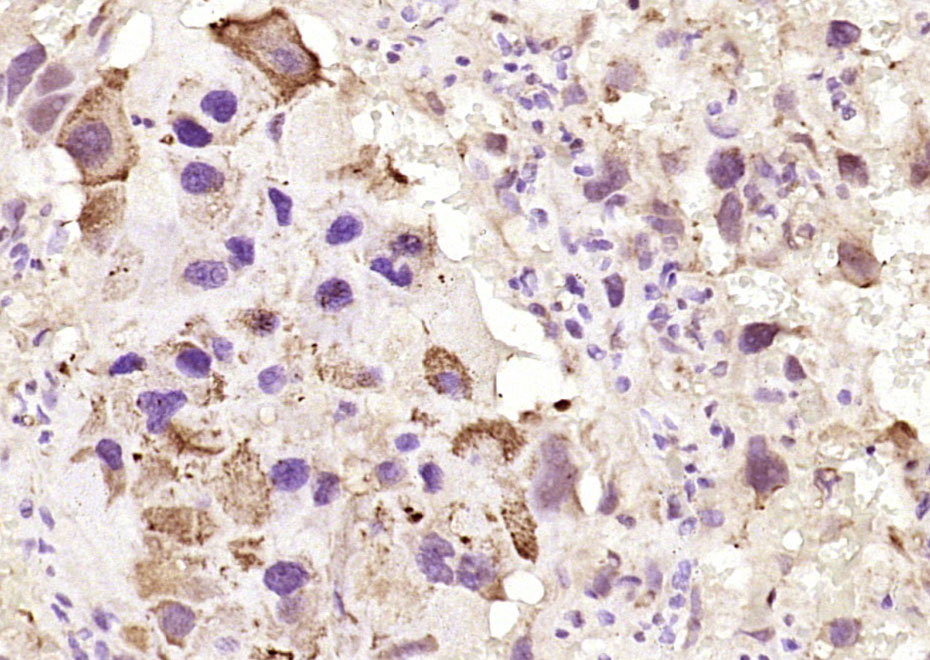

Paraformaldehyde-fixed, paraffin embedded (rat placenta); Antigen retrieval by boiling in sodium citrate buffer (pH6.0) for 15min; Block endogenous peroxidase by 3% hydrogen peroxide for 20 minutes; Blocking buffer (normal goat serum) at 37°C for 30min; Antibody incubation with (GPX3) Polyclonal Antibody, Unconjugated (bs-22009R) at 1:400 overnight at 4°C, followed by operating according to SP Kit(Rabbit) (sp-0023) instructionsand DAB staining.